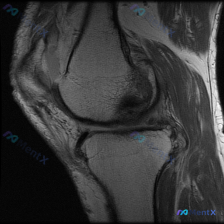

这是一份单张膝关节矢状位MRI影像,临床关注点是"半月板异常",需要基于现有影像做分析。

- 序列与定位:膝关节中部偏内侧矢状位,考虑为PDWI或T1加权像,适合显示半月板、韧带解剖结构

- 骨骼结构:股骨远端、胫骨近端骨皮质连续,骨髓信号均匀,无明显骨挫伤、骨折征象,软骨下骨面平整

- 半月板:本层面可见部分半月板体部,形态为典型低信号领结状,未见异常信号延伸至关节面,无明确撕裂征象

- 交叉韧带:前、后交叉韧带走行连续,形态张力正常,无水肿、中断表现

- 其他结构:关节腔无明显异常积液,髌下脂肪垫、股四头肌腱、髌腱均未见明显异常